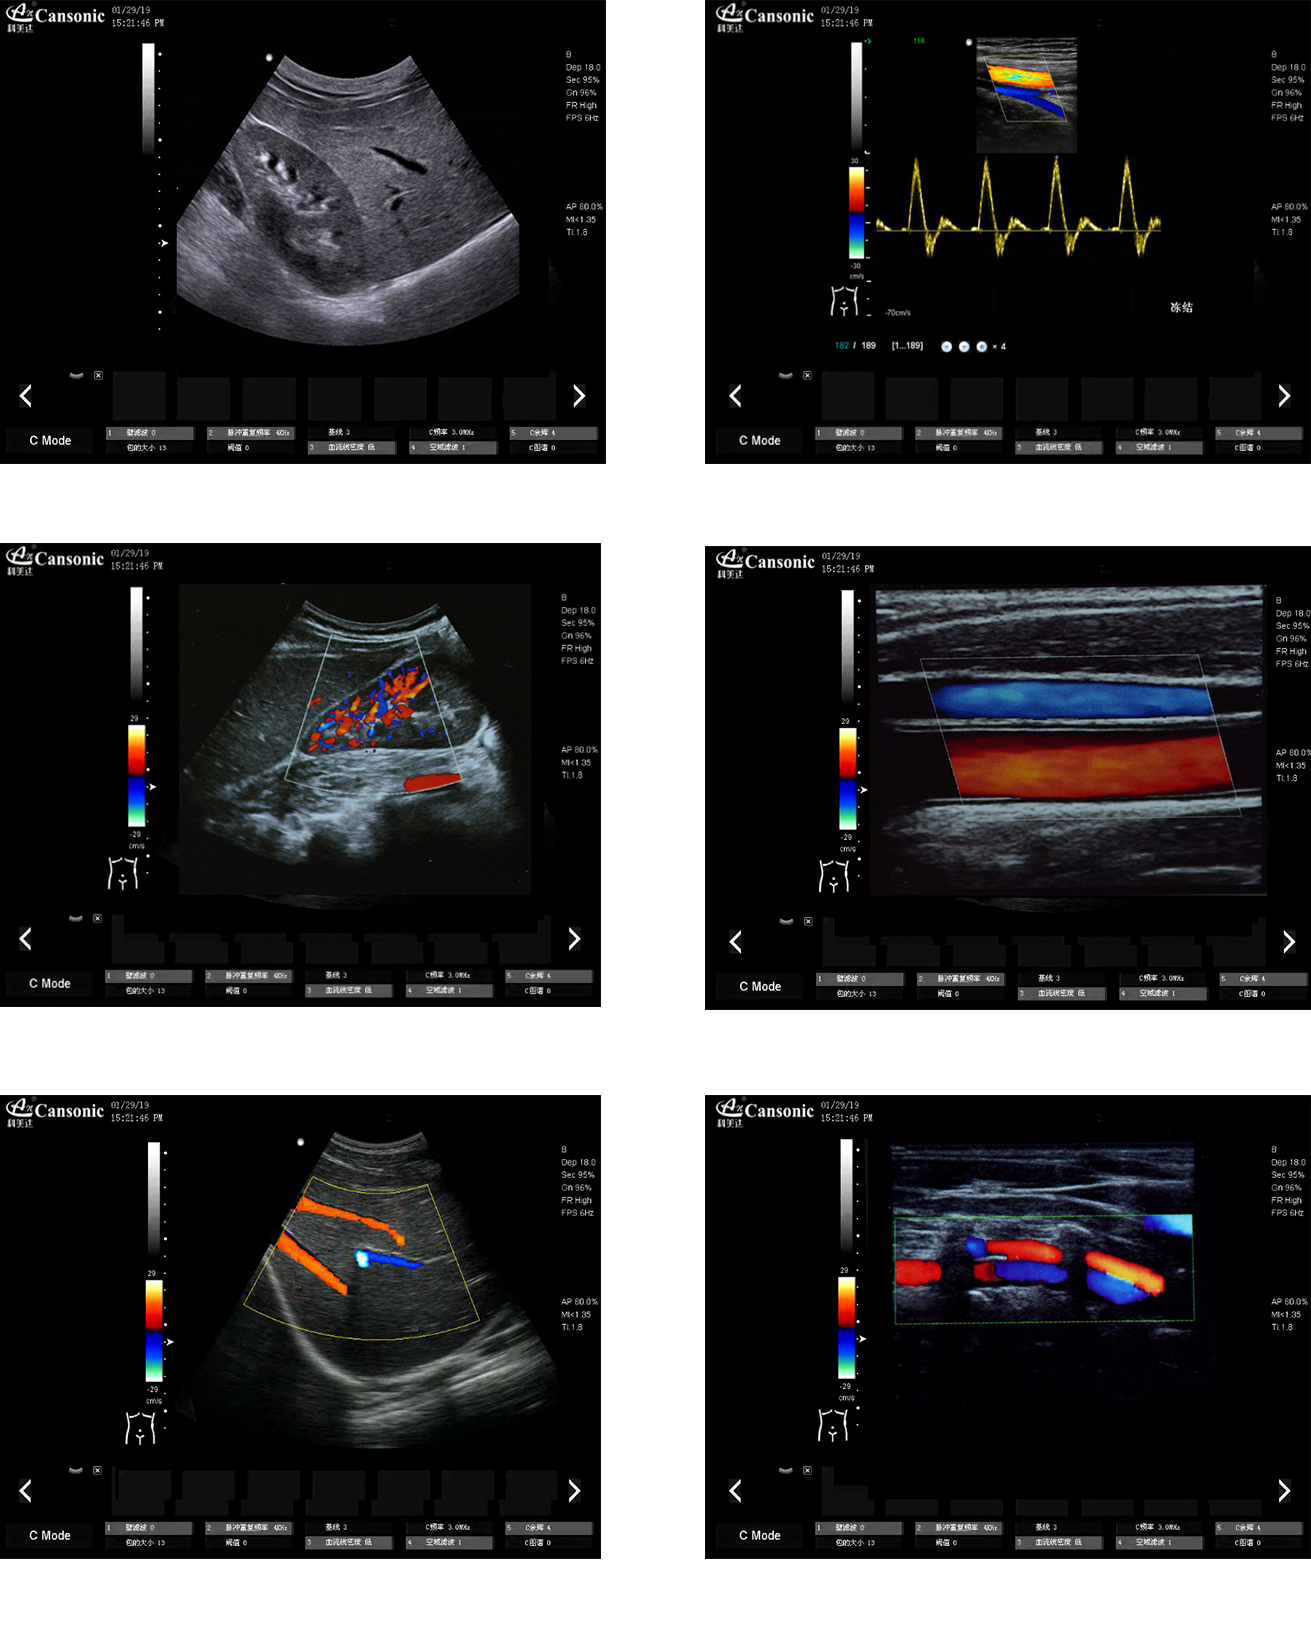

科美達(dá)K22圖像實例

K22

1、全身應(yīng)用型彩超,擁有完善的臨床應(yīng)用解決方案

2、高倍波束并行處理系統(tǒng),使超聲顯像更流暢

3、諧波融合成像技術(shù),提高近場分辨率的同時保證遠(yuǎn)場穿透率

4、陣列設(shè)計探頭技術(shù),有效提高細(xì)節(jié)分辨率和圖像的細(xì)膩度,

5、高分辨率灰階血流成像,提升對微細(xì)血管的血流探測靈敏度,對大血管管壁成像及管壁斑塊的診斷也有很大幫助

6、iClear 智能斑點噪聲抑制技術(shù),有效抑制旁瓣偽像,提高診斷正確率